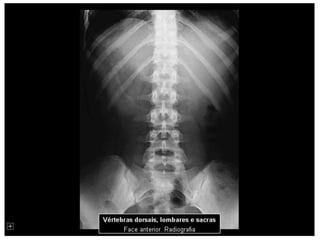

Esqueleto 1

Aula de anatomia acerca do esqueleto Humano 1